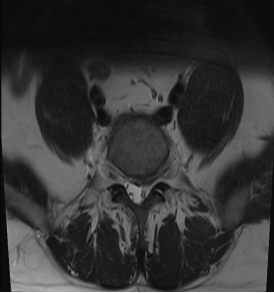

作为目前骨科领域领先的脊柱微创技术,UBE技术通过建立两个直径仅0.5—0.7cm的微小通道,将内镜、操作器械分别置入。医生可通过高清内镜画面,清晰观察脊柱内部的病变组织——无论是突出的椎间盘、狭窄的椎管,还是增生的骨赘,都能在放大视野下一目了然。相较于传统开放手术,UBE技术实现了“小切口解决大问题”:术中出血极少,创伤面积不足传统手术的1/5,术后疼痛轻,患者可快速下床活动,住院时间缩短至3—5天,极大降低了术后感染、粘连等并发症风险,尤其适用于腰椎间盘突出症、腰椎管狭窄症等常见及复杂脊柱疾病,让脊柱治疗告别“大动干戈”,迈入微创精准诊疗时代。

如果说UBE技术是脊柱治疗的“精准镜手”,那么3D打印技术就是定制化治疗的“私人裁缝”。针对每一位脊柱疾病患者的个体差异,医生通过高精度CT扫描,获取患者脊柱的三维立体数据,利用3D打印技术1:1还原脊柱的解剖结构——从椎体形态、椎间盘位置,到神经走行、病变范围,都能精准复刻,形成专属的脊柱模型。基于此模型,医生术前可以进行精准规划:模拟手术路径、预判操作风险、选择适配的内固定器械,甚至打印定制化的椎间融合器、内固定支架,确保手术操作“有的放矢”,贴合患者的个体解剖特征,避免传统手术中“凭经验操作”的不确定性,让脊柱治疗从“标准化”走向“个性化”,极大提升了手术的精准度与安全性。